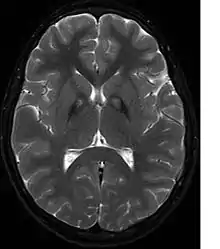

MRI image shows iron deposits in the basal ganglia, the so-called eye-of-the-tiger sign (T2w GRASE sequence).

A neurological examination would show evidence of muscle rigidity; weakness; and abnormal postures, movements, and tremors. If other family members are also affected, this may help determine the diagnosis. Genetic tests can confirm an abnormal gene causing the disease. However, this test is not yet widely available. Other movement disorders and diseases must be ruled out. Individuals exhibiting any of the above listed symptoms are often tested using MRI (Magnetic Resonance Imaging) for a number of neuro-related disorders. An MRI usually shows iron deposits in the basal ganglia. Development of diagnostic criteria continues in the hope of further separating PKAN from other forms of neurodegenerative diseases featuring NBIA.

Microscopic features of PKAN include high levels of iron in the globus pallidus and the pars reticulata of substantia nigra, evident as a characteristic rust-brown discoloration[6] in a pattern called the eye-of-the-tiger sign;[7] lipofuscin and neuromelanin concentrated in the iron-accumulating areas; oval, nonnucleated structures representing swollen axons whose cytoplasm swells with vacuoles, referred to as spheroids, axon schollen, or neuroaxonal dystrophy; and Lewy bodies.[6]